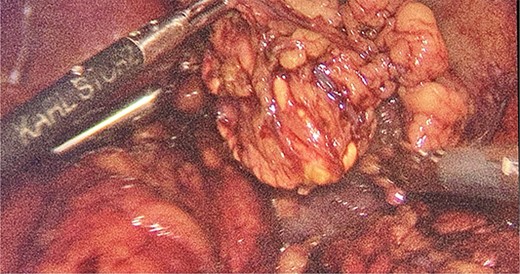

We had to first liberate the adhesions of the colon from a previous operation before gaining entry to the left colon. To do so, we made an incision in the White line of Toldt and dissected the right gastrocolic and splenocholic ligaments. This allowed us to access the retrocolic space and approach the left kidney. We identified the left renal vein and the left suprarenal gland and dissected the gland from the fatty tissue of the kidney. The gastrosplenic ligament was also liberated through the ligation of short gastric arteries. After separating the stomach from the posterior abdominal wall, we located the GIST (Fig. 3) on the posterior part of the fundus and removed it through wedge resection (Fig. 4).

After the surgery, she was closely monitored for any possible complications. There were no signs of intra-abdominal bleeding, high blood pressure, intra-abdominal infection, abscess, or delayed wound healing. As a result, the patient was discharged from the hospital on the 14th day following the surgery. During the follow-up, the patient had her blood pressure and hormone levels normalized. The follow-up results showed that the aldosterone at rest was 14.2 ng/dL. She also reported withdrawal of headaches and stomach pains. The pathological result came in as micro- and macronodular hyperplasia of the left suprarenal gland and GIST with a very low risk of progression.